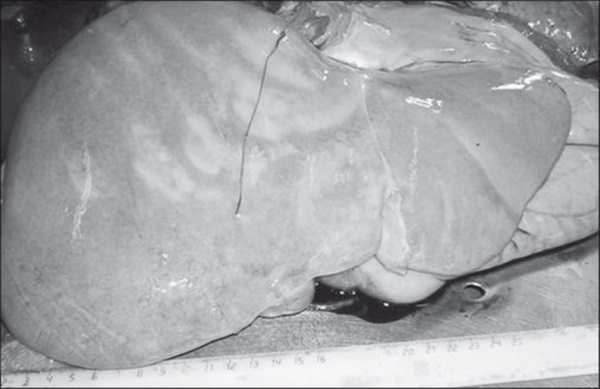

Рис. 25. Стеатоз печени